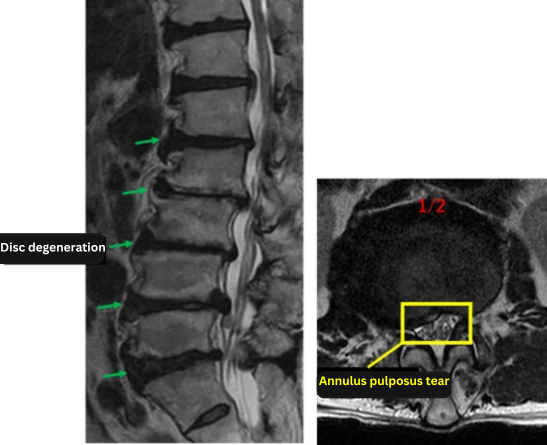

Imaging and findings

L1/2: Disc degeneration, bulging, left foraminal stenosis, annular tear

L2/3: Disc degeneration, bulging, bilateral foraminal stenosis, endplate degeneration

L3/4: Disc degeneration, bulging, bilateral foraminal stenosis, endplate degeneration

L4/5: Disc degeneration, bulging, right foraminal stenosis, endplate degeneration

L5/S1: Disc degeneration, bulging, bilateral foraminal stenosis, endplate degeneration

The above findings were also observed on the imaging.

The symptoms—specifically the intermittent claudication and high pain levels—were likely caused by the cumulative pressure from disc bulging and stenosis at every level from L1/2 to L5/S.